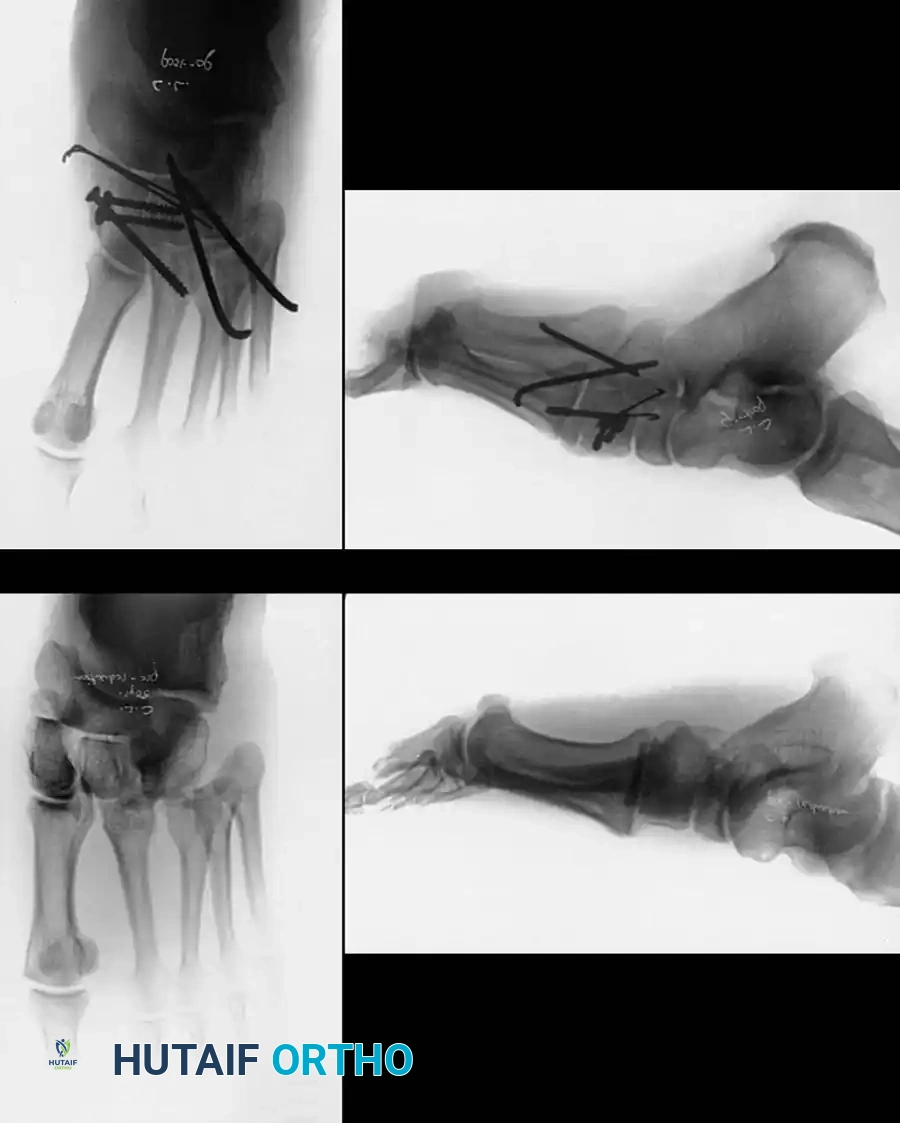

METATARSALS Surgical Diagram

Fig. 86-42 Divergent Lisfranc fracture-dislocation. A and B, Preoperative radiographs demonstrating intercuneiform and naviculocuneiform disruption. C and D, Postoperative radiographs following intracuneiform arthrodesis for stabilization in a high-BMI patient. This highlights the spectrum of severe midfoot trauma that often accompanies or parallels metatarsal injuries.

Fig. 86-43 A-D. A, Type IA, acute fracture of the proximal diaphysis of the fifth metatarsal. B-D, Type II fractures demonstrating varying degrees of sclerosis and canal obliteration.

Fig. 86-43 E-F. E, Type IIIA, fracture of the styloid process without articular involvement. F, Type IIIB, fracture of the styloid process with joint involvement.